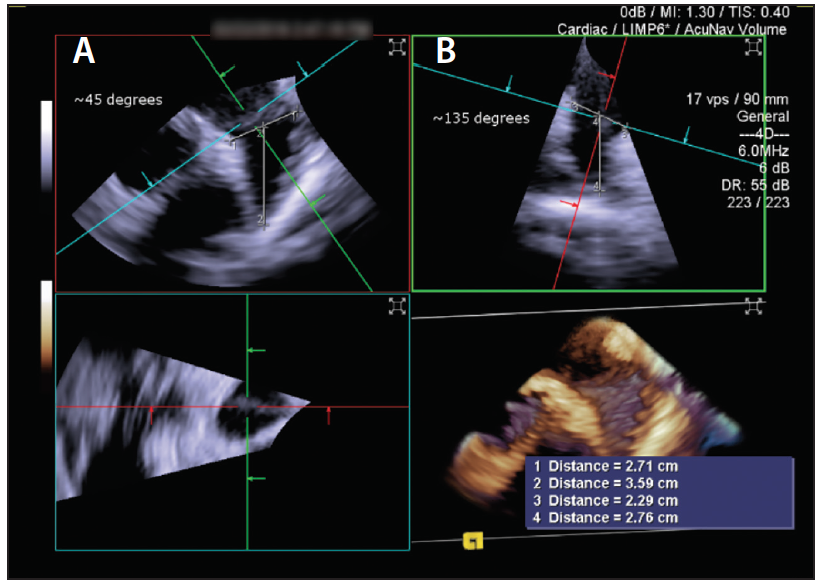

One of the concerns with such manipulations of the ICE probe in the left atrium is the risk of inadvertent injury, particularly in the thin-walled left upper pulmonary vein. Hence, a more recent advance is the utilization of 3D ICE, which obtains not only 3D reconstructed imaging (Figure 4 and Figure 5) but also, importantly, has the ability to do multiplanar reconstruction. All of these views by the 3D ICE probe can be achieved from a midleft atrial position, therefore obviating the need for aggressive probe manipulations in the left atrium and left pulmonary veins. A potential downside of the ICE probes remains their costs and impact on reimbursement.

Figure 4. Multiplanar reformatting can be used to align the LAA. Panel A shows a 45° view of the LAA and panel B corresponds to a 135° orthogonal view.